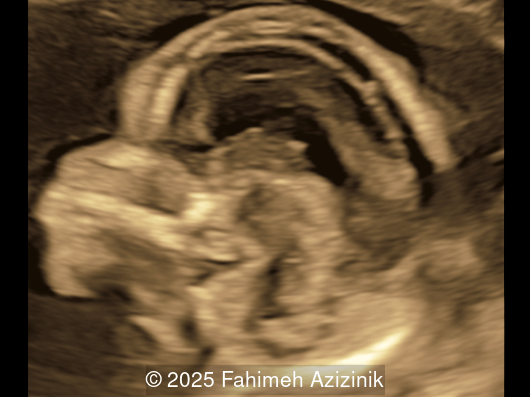

Image 2

Video 2 © 2025 Fahimeh Azizinik

• Bicoronal craniosynostosis

• Hypertelorism

Bicoronal synostosis is the characteristic cranial hallmark of Apert syndrome, detectable sonographically from 18 weeks. Its most recognizable manifestation is turribrachycephaly, defined by an elevated cephalic index (typically >85–90%) and a tall cranial vault with marked frontal bossing [19]. On prenatal ultrasound, the face in Apert syndrome shows midface hypoplasia with a depressed nasal bridge, proptosis, hypertelorism, and frontal bossing. The extremities demonstrate syndactyly of both bone and soft tissue of the hands and feet with partial-to-complete fusion often involving second, third, and fourth digits, known as “mitten hands” and “socked feet”. In severe cases, all digits are fused, with the presence of a single nail known as “synonychia” [20]. Other ultrasound findings include mild ventriculomegaly, agenesis of the corpus callosum, deficient or absent septum pellucidum, and fusion of the cervical vertebrae at the level of C5-C6 [21]. Cardiovascular (atrial and ventricular septal defect) and genitourinary anomalies (hydronephrosis, and cryptorchidia) are present in 10% of patients [22]. Increased nuchal translucency in the first trimester [23], widely open metopic suture [24], and polyhydramnios [25] have also been reported. Three-dimensional (3D) ultrasound facilitates assessment of surface abnormalities of the face and extremities, and magnetic resonance imaging (MRI) can be used to evaluate associated intracranial conditions [26].